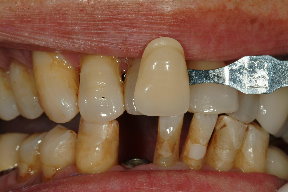

經過四週後,由於傷口癒合良好,準備製作假牙,由於是前牙區,因此顏色相當重要,因此使用數位比色(圖六)及數位攝影(圖七),取得牙齒之精確顏色分佈。

經裝戴完成,患者複診後,植牙之美觀與功能皆符合患者之期待(圖八、圖九)